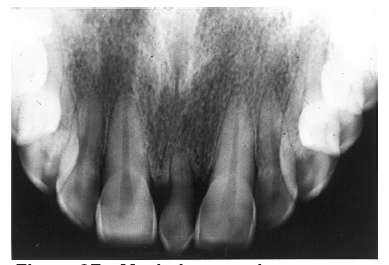

Figure 2 - Advanced Enamel Caries

Figure 2

While advanced dental caries may well involve the entire tooth, early or incipient caries involves only the enamel. Once a carious lesion penetrates through the enamel, it is usually considered to be dentinal caries. Clinically, enamel caries usually appears as a stained system of occlusal grooves or as chalky white bands along the labial/buccal gingival aspects of the teeth. Radiographically, enamel caries is characterized by a focal loss of the normal enamel radiopacity, particularly on the interproximal surfaces.

It appears as a radiolucent cone shape, with the base at the exterior surface and the tip of the cone toward the pulp. The lesion follows the enamel rods. After progression into the dentin the lesion usually takes on a radiolucent fan shape.

Figure 2 illustrates advanced enamel caries on the mesial surface of the premolar.